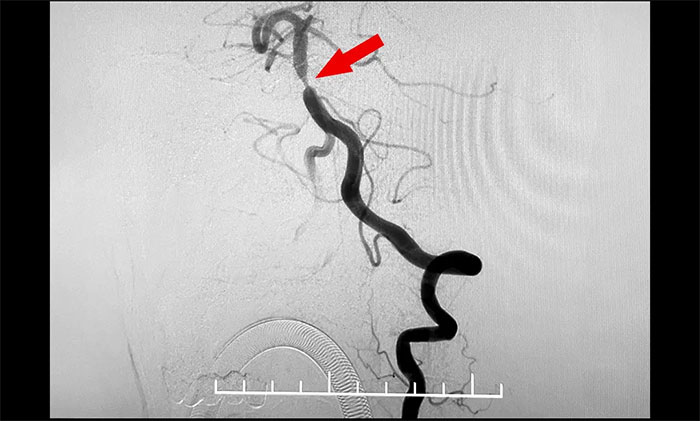

头颅MRI+SWI+DTI提示脑干梗塞,双侧桥臂变性;双侧放射冠区、额顶叶散在腔梗、缺血灶。基底动脉HRMR平扫+增强提示基底动脉管壁增厚伴重度狭窄。头颅CTP显示,右侧顶枕颞叶局部脑组织灌注较对侧稍减低。DSA提示基底动脉中段重度狭窄。

▲ 基底动脉重度狭窄